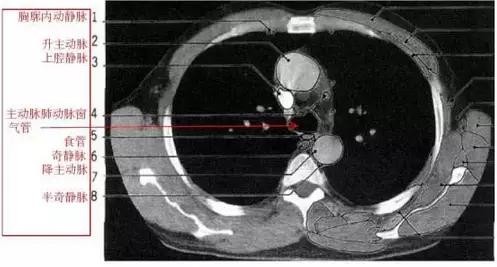

胸部的CT是通过X线计算机体层摄影(CT)对胸部进行检查的一种方法。正常胸部CT层面较多,每一层面结构所表现的图像不同。下面是胸部CT图文示意图,可帮助临床医生详细了解CT结构。我们一起来看一下吧。